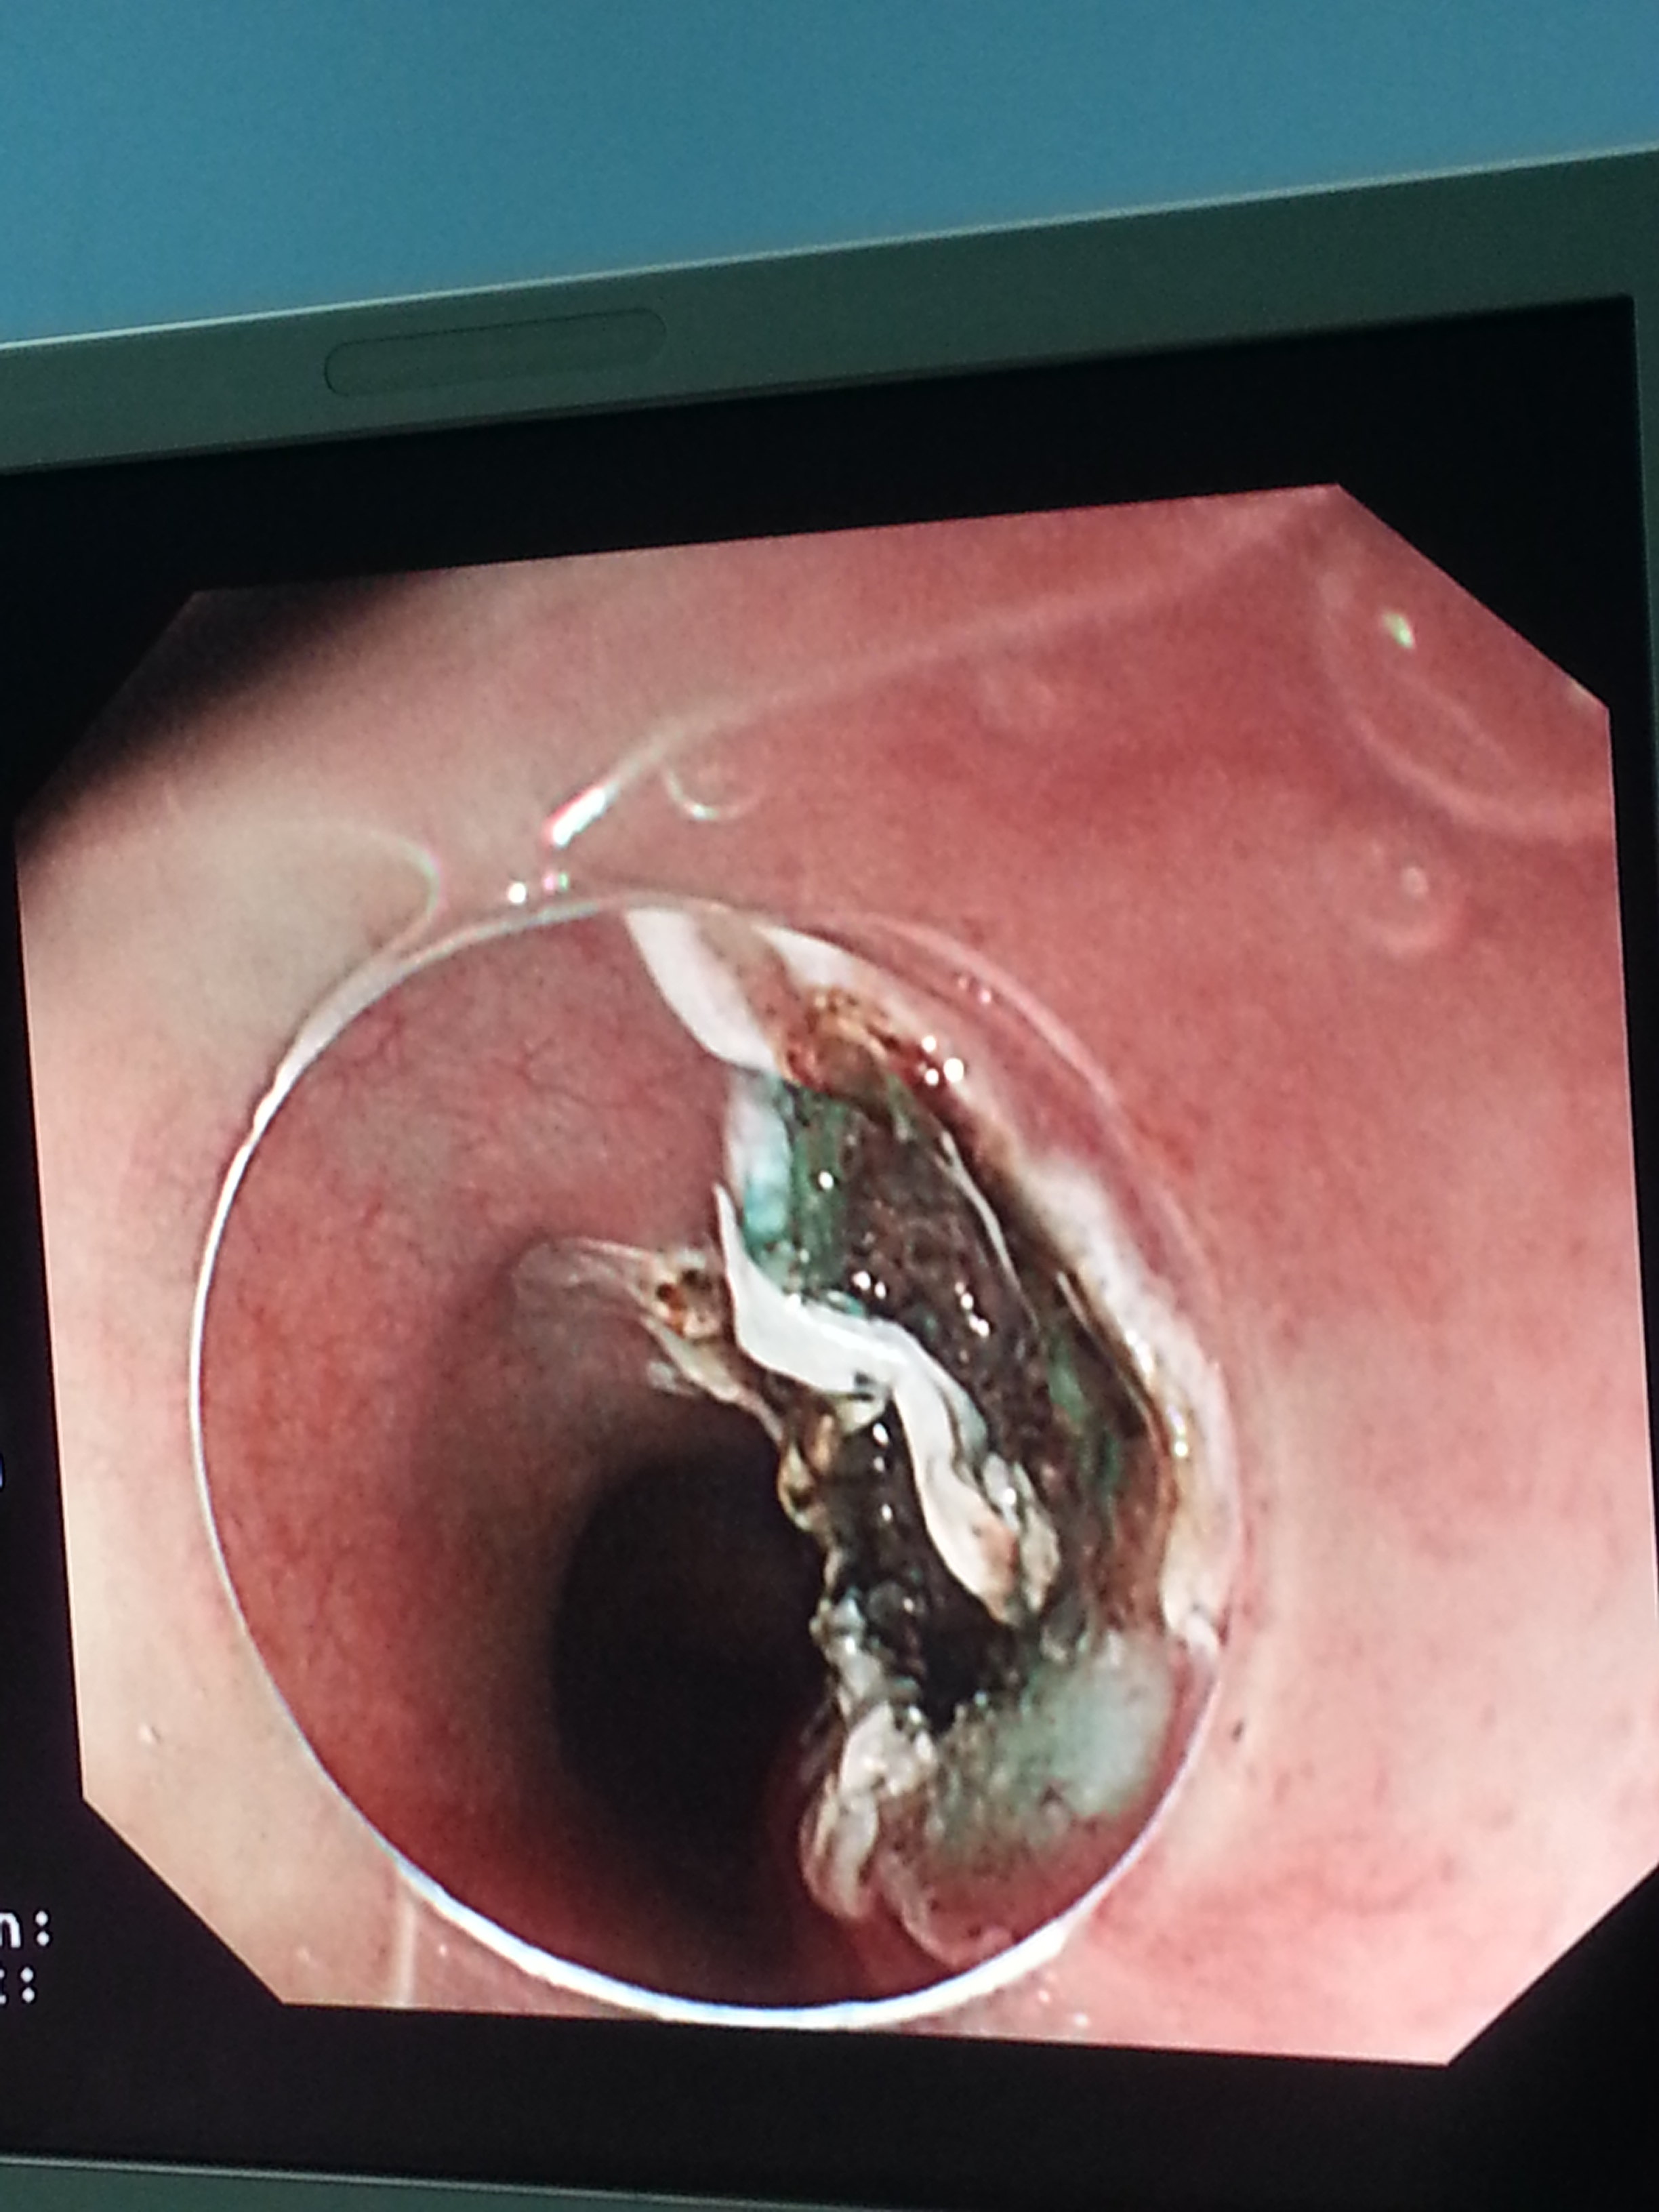

食管平滑肌瘤esd术

图片尺寸2448x3264